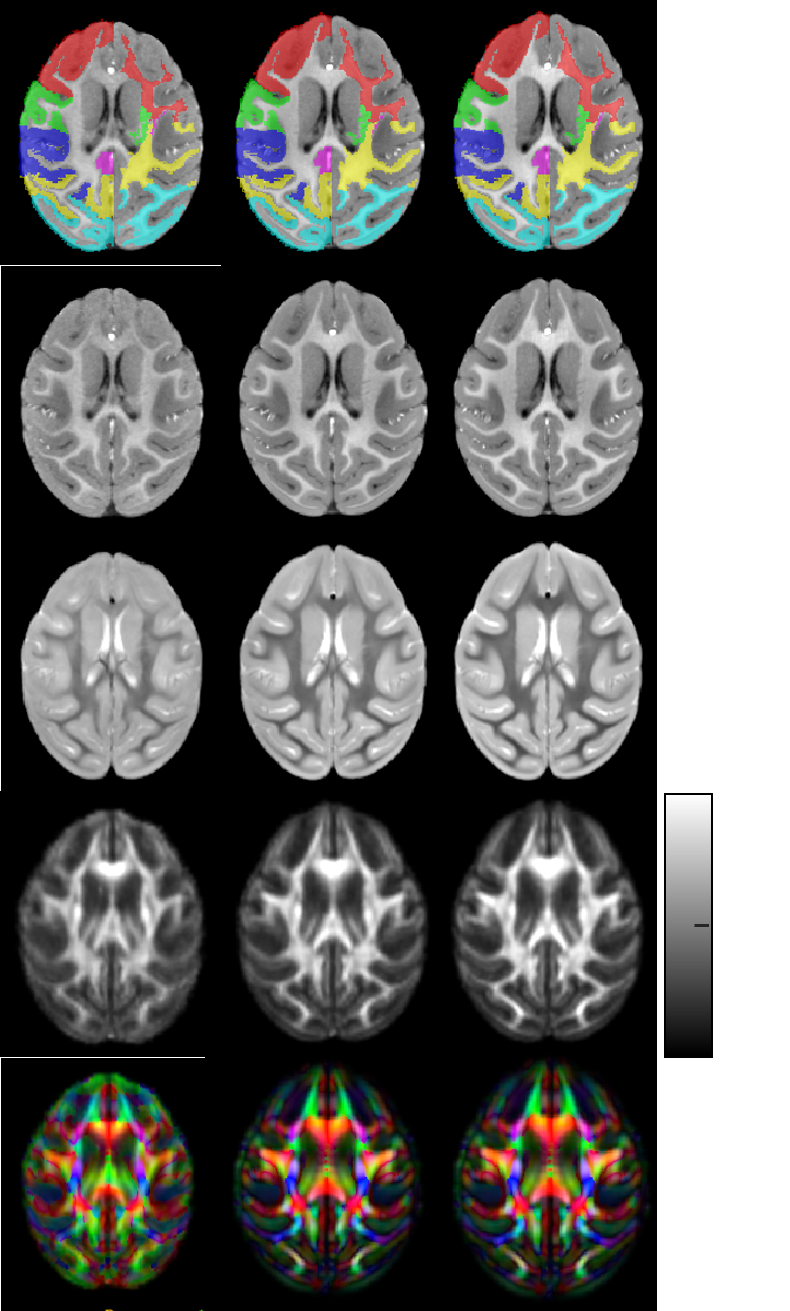

ONPRC Infant Macaque Brain Atlas Images

1 Images available.

Description: